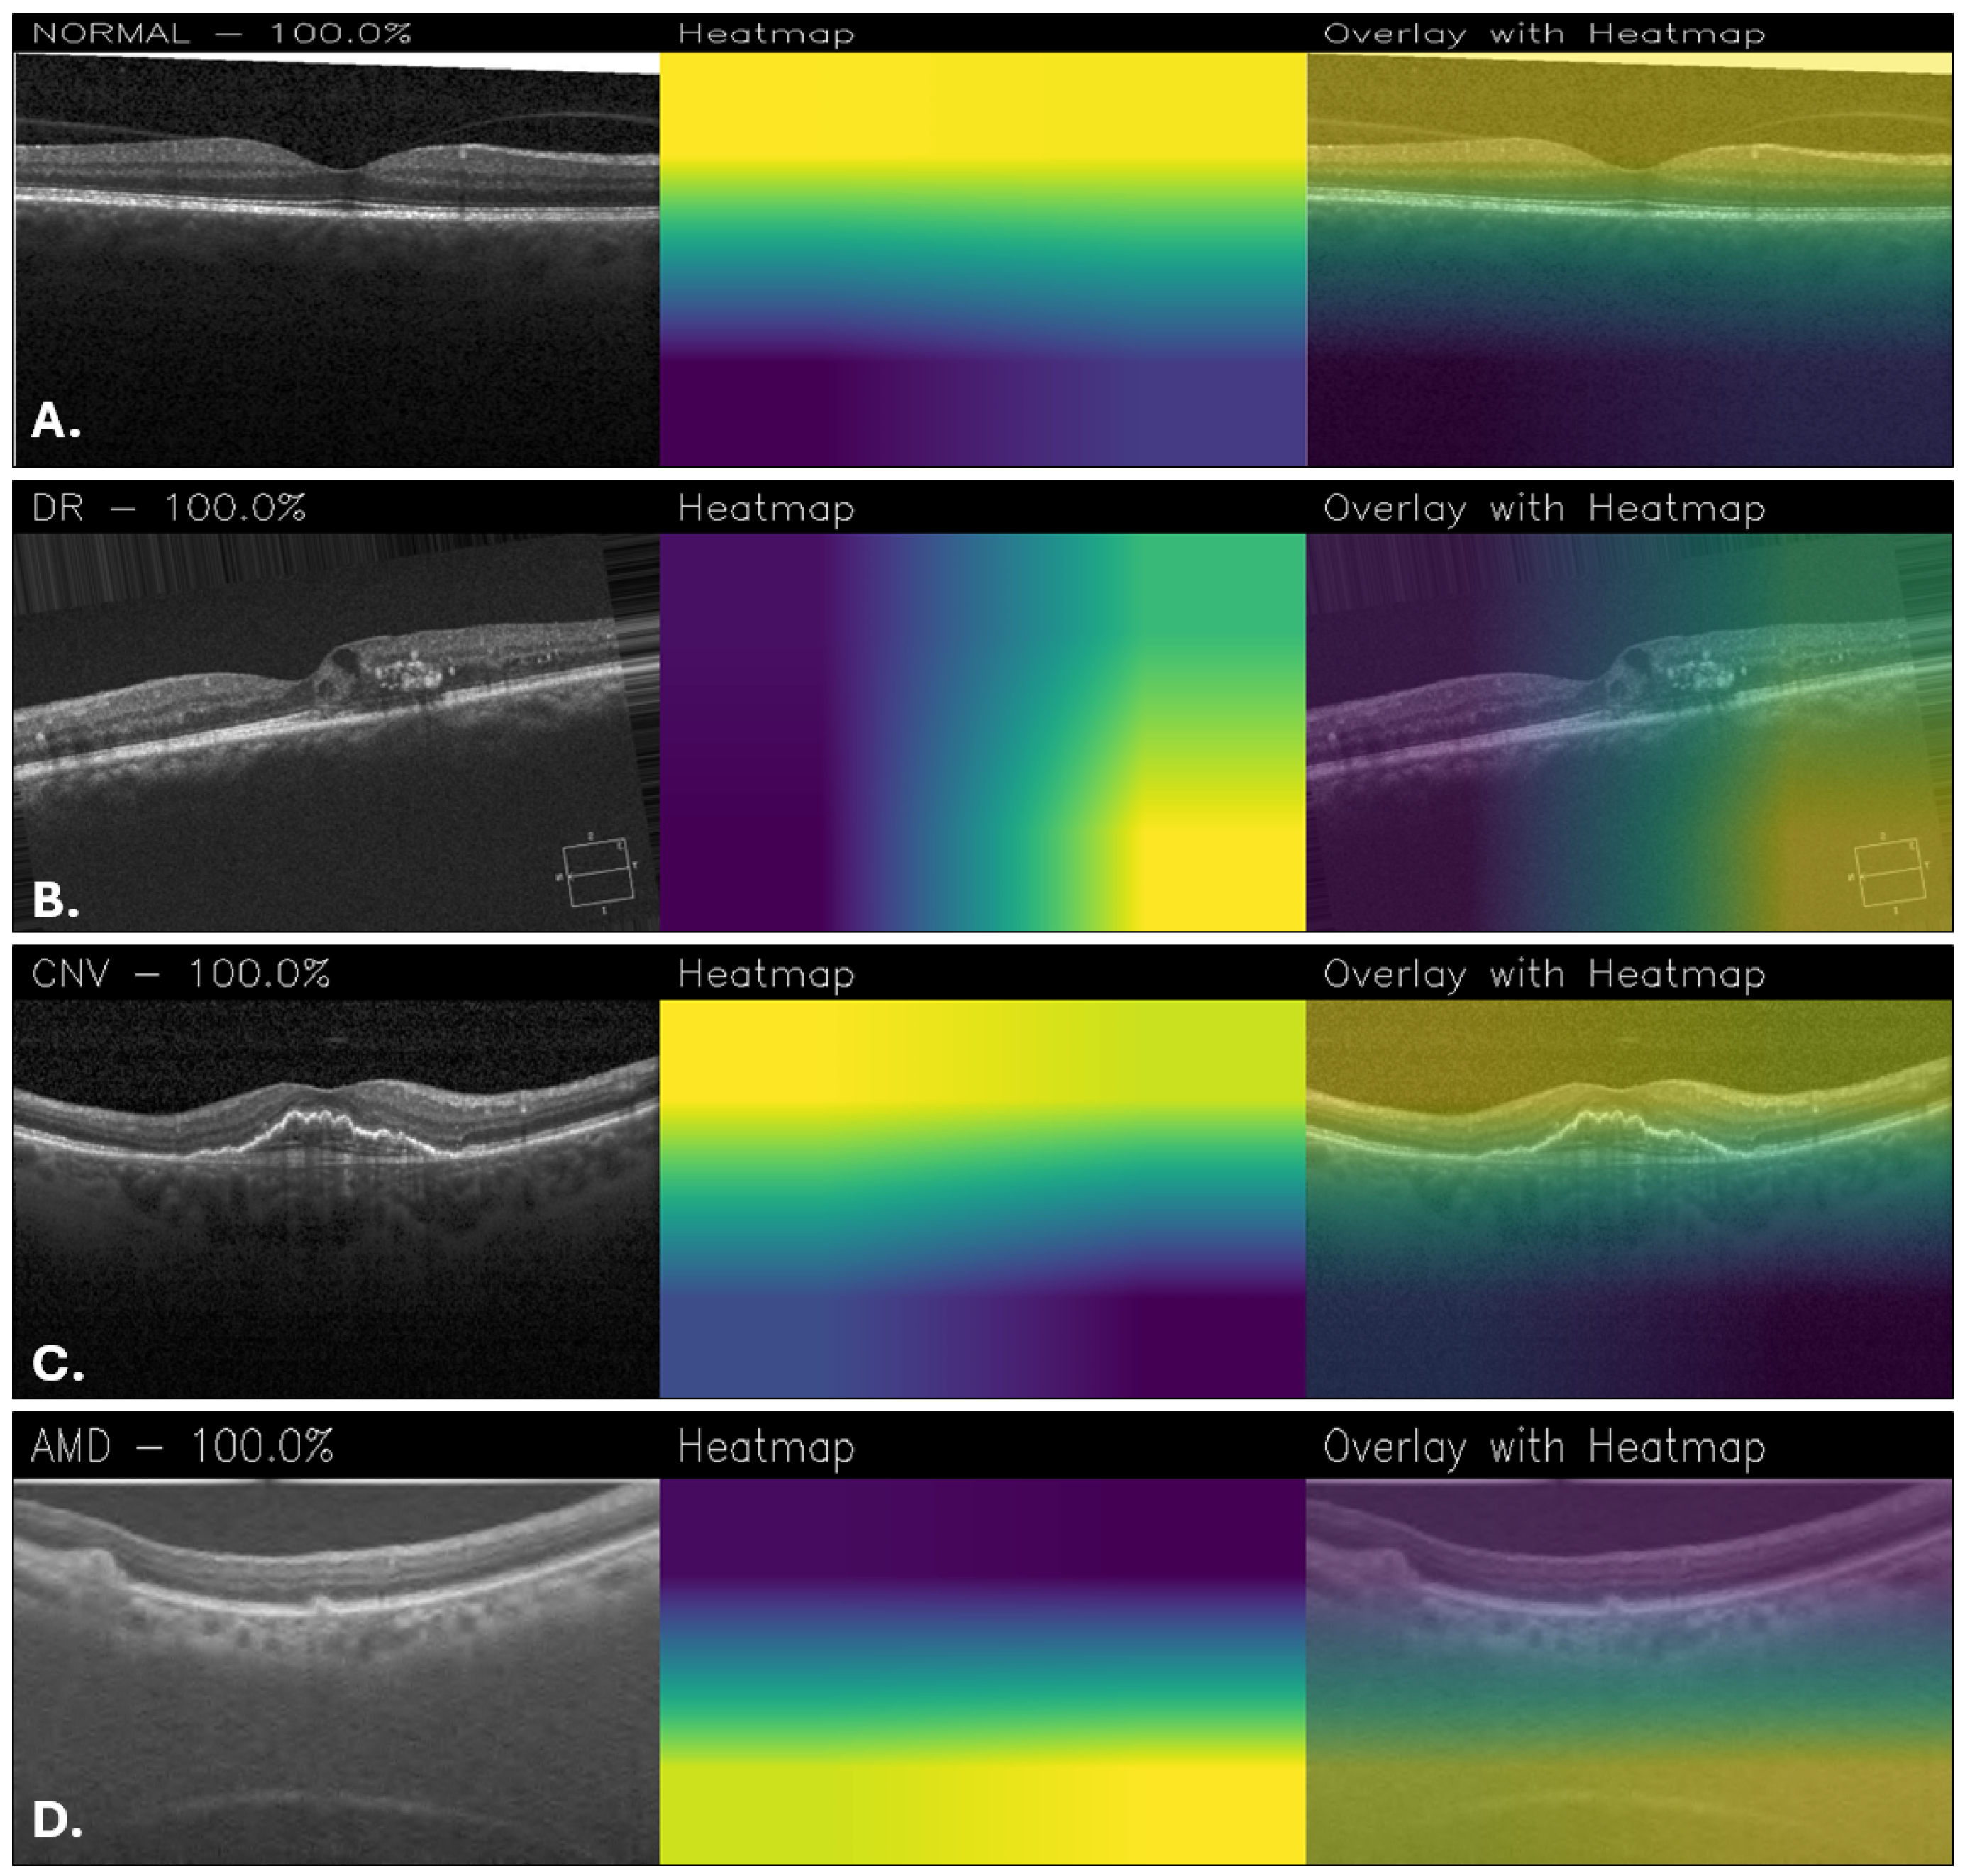

Figure 11, on the other hand, shows examples of classifications made using the Custom_CNN model. In the normal retina, Figure 11A showed minimal activation, limited to the foveal contour. In DR (Figure 11B), attention was directed to retinal thickening and hyperreflective foci consistent with exudates, even if there are some parts of the heatmap that are noisy. For CNV (Figure 11C), activation was localized to the subfoveal lesion and subretinal space. Finally, in the AMD case (Figure 11D), activation was more diffusely distributed along the retinal pigment epithelium, reflecting drusen and pigment epithelial changes.

Figure 11. Grad-CAM visualizations obtained with the Custom_CNN for healthy retina (A), DR (B), CNV (C), and AMD (D).